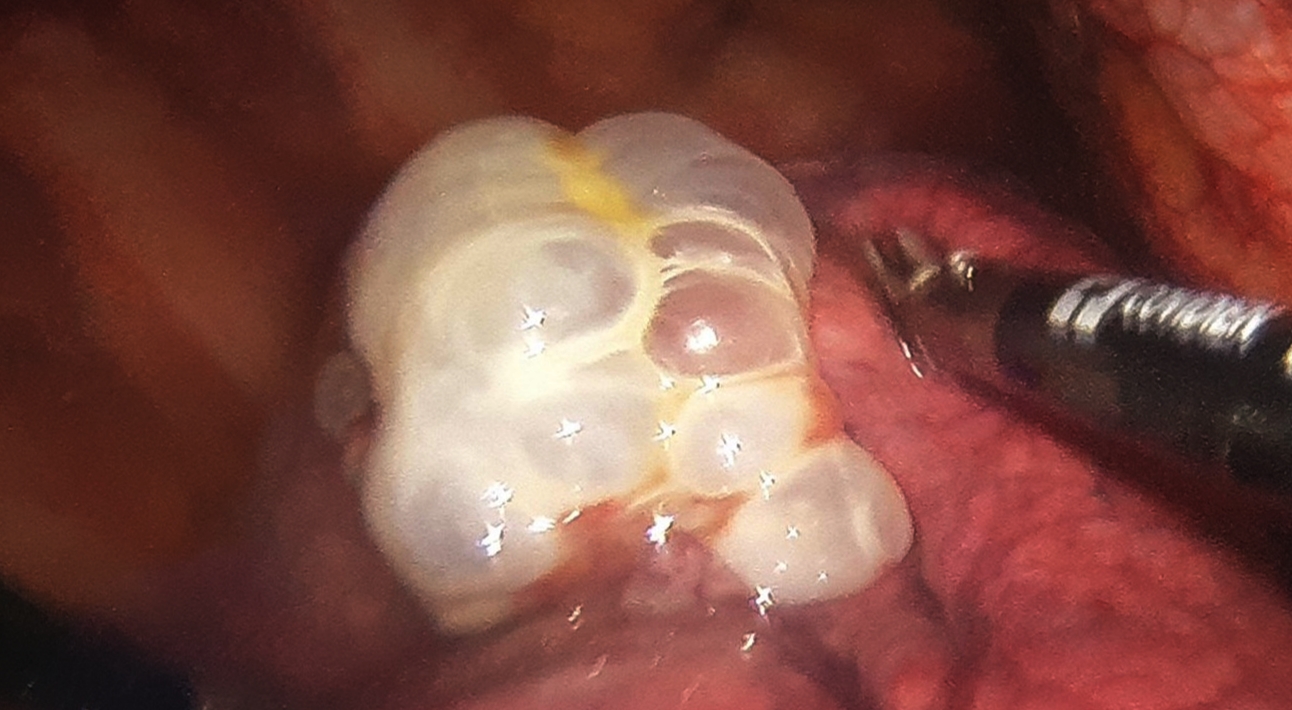

Hình ảnh kén khí phổi bệnh nhân trong lúc phẫu thuật. Ảnh: BS cung cấp

Sau 5 ngày được chăm sóc nâng cao thể trạng, chuẩn bị về thể chất và tinh thần, người bệnh được phẫu thuật lồng ngực có nội soi hỗ trợ để cắt kén khí ở 3 vị trí, bảo tồn tối đa nhu mô lành, tạo dính màng phổi để đề phòng tái phát. Kết quả sau phẫu thuật sức khỏe người bệnh được cải thiện tích cực, giảm đau ngực và hết khó thở.